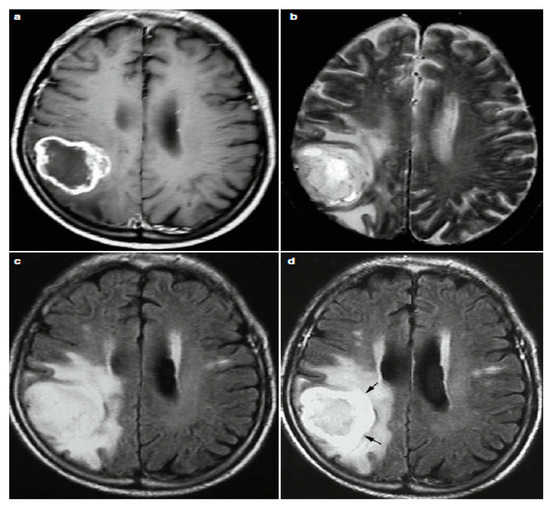

2.3. Reading MRI Sequences